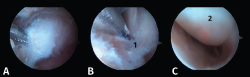

Figura 4. A: imagen artroscópica que muestra el ligamento peroneo-astragalino posterior (LPAP) (1); B: resección del LPAP con un sinoviotomo orientado medialmente contra la cara lateral del proceso posterolateral del astrágalo (PPA) (2); C: cara lateral del PPA después de la resección del LPAP.

- Primer paso: retirar el LPAP, completamente en caso de PPAH y parcialmente en caso de OT. La resección del tejido ligamentoso se realiza apoyando la ventana del sinoviotomo contra el lateral del PPA (Figuras 4 A, B y C).

- Tercer paso. El sinoviotomo se gira ahora para que la ventana vuelva a mirar la cara medial del PPA. En este momento, el tendón FHL permanece medial al sinoviotomo y opuesto a su ventana. Podemos así seccionar el retináculo del FHL con el sinoviotomo o mediante una pinza de tipo basket (Figuras 6 A, B y C).

Figura 6. A y B: liberación del retináculo del flexor hallucis longus (FHL) (1); C: evaluación del interior de la vaina del FHL (2).